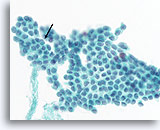

Afbeelding 86

Medullair schildkliercarcinoom, schildklier FNA, celblok.

Deze kleuring van het weefsel in afbeelding 80-85 met Congo-rood markeert een fragment amyloïde.

60X

Afbeelding 86

Medullair schildkliercarcinoom, schildklier FNA, celblok.

Deze kleuring van het weefsel in afbeelding 80-85 met Congo-rood markeert een fragment amyloïde.

60X